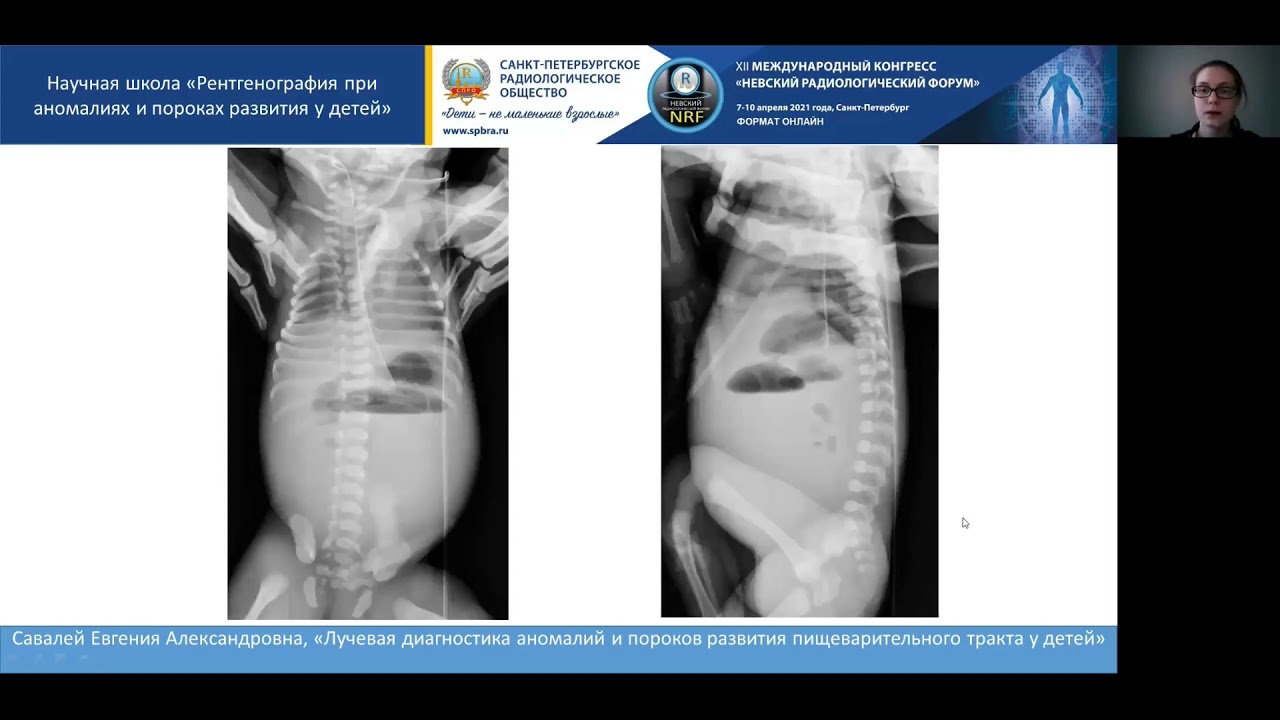

Что покажет рентген грудной клетки

- Сразу после родов в пораженной половине грудной клетки определяется уплотнение, соответствующее мягким тканям — диафрагмальная грыжа пищевода

- Позднее, после родов, в грудной клетке определяются заполненные газом петли кишечника

- Купол диафрагмы на стороне поражения не идентифицируется

- Заметно относительно небольшое количество газа в брюшной полости

- Гипоплазия легкого на стороне поражения

- Смещения средостения в противоположную сторону

- При поздних формах диафрагмальной грыжи пищевода первоначально кардиопульмональные признаки в пределах нормы

- Желудочно-кишечная трубка выходит в грудную полость (необходимость во введении контрастного вещества обычно отсутствует)

- При правосторонней врожденной диафрагмальной грыже в грыжевой мешок выходит печень, кишечник — редко.